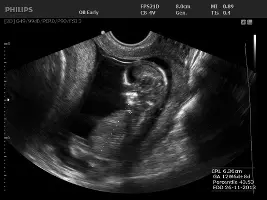

Usluge ordinacije obuhvaćaju ginekološke preglede, porodništvo, ultrazvučnu dijagnostiku, ginekološki ultrazvuk: 3D i 4D ultrazvuk. 4D ultrazvučni prikaz najčešće korišten u trudnoći, osim jasnog prikaza izgleda ploda pruža najdetaljniji uvid u morfologiju i anatomiju fetusa. Od 3D prikaza razlikuje se utoliko jer omogućuje prikaz slike u stvarnom vremenu te samim time i bolji uvid u dinamiku i stanje ploda.

3D i 4D ultrazvuk dio je onoga što na raspolaganju ima GINEKOLOŠKA ORDINACIJA DR. IGOR LONČAR. Obratite se s povjerenjem!